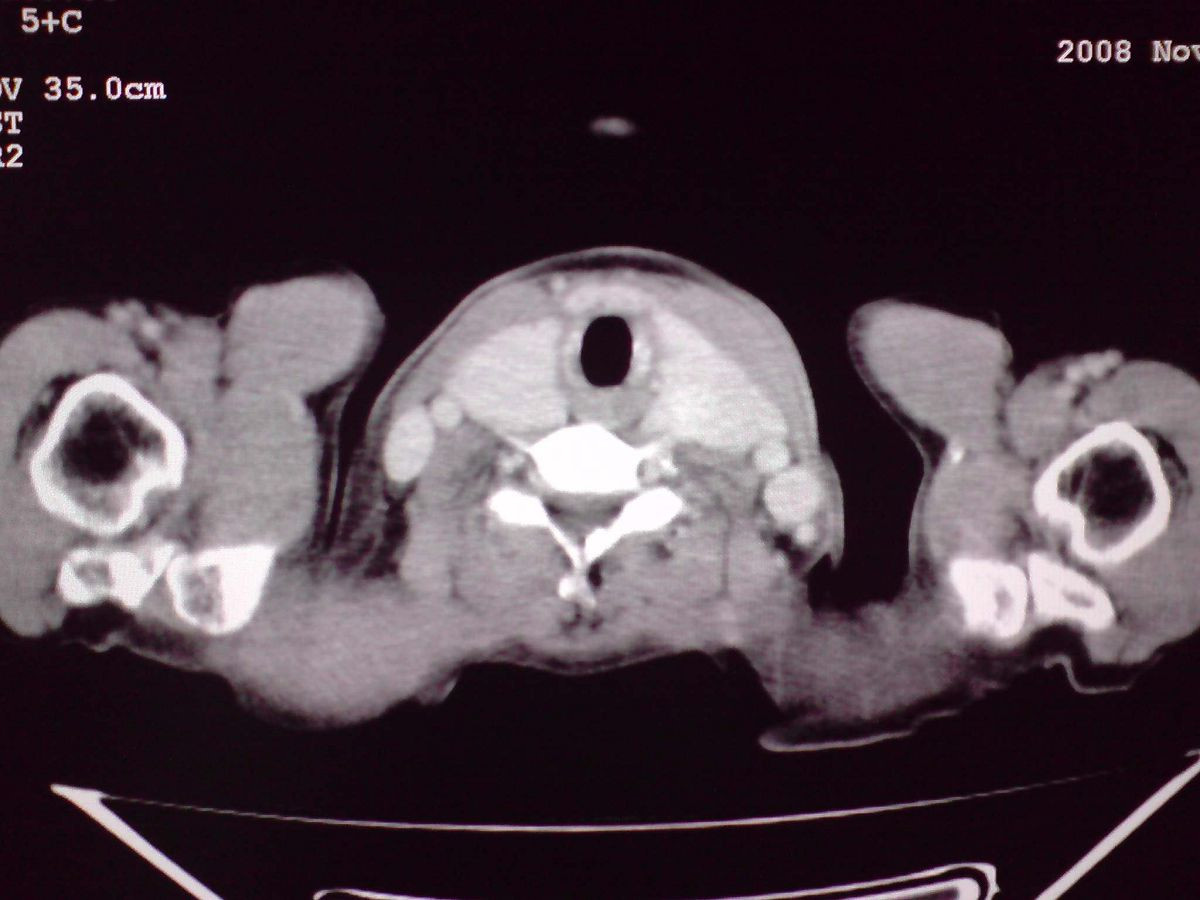

患者女性,65岁,无明显不适,甲状腺功能无异常

结节状甲状腺肿,部分突入胸腔,形成胸内甲状腺

双侧甲状腺肿大,向下部分突入胸腔,双侧甲状腺内密度不均,可见结节状低密度影,并见散在斑点状钙化,增强后病灶实性部分强化明显,气管受压稍变窄左移。

考虑:双侧甲状腺腺瘤可能,不除外甲状腺癌。

胸内甲状腺,双侧结节状甲状腺肿伴右侧甲状腺腺瘤。

甲状腺左右叶增大,并向下突入胸腔内,其内可见多发条片状钙化影及囊性低密度影,邻近组织及血管无浸润、包埋征像,双侧结节性甲状腺肿伴右侧甲状腺腺瘤形成可能性大,甲状腺癌待排;因病人就要手术,期待结果。